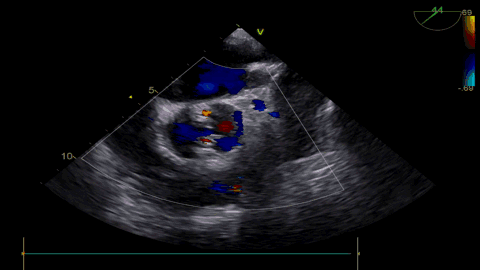

更换VenusA26号瓣膜前1/3

VenusA26号完全释放

最后一枪造影

超声显示人工瓣膜工作良好,微量瓣周漏,术后一周顺利出院,术后随访无并发症,恢复良好。